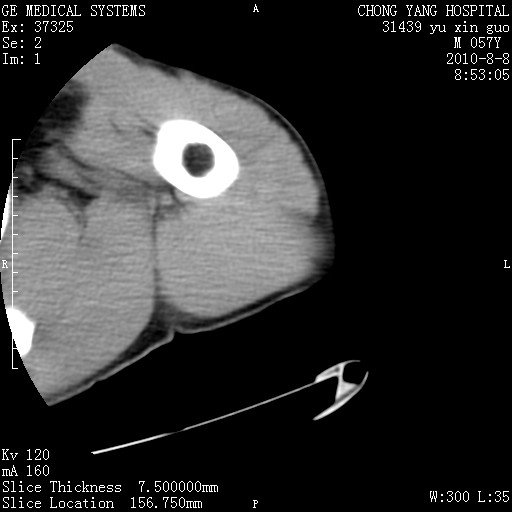

标题: CT28267:M57Y 上臂包块8年余。 [打印本页]

标题: CT28267:M57Y 上臂包块8年余。

典型脂肪瘤改变

包膜光滑、完整的脂肪密度肿块,支持脂肪瘤。